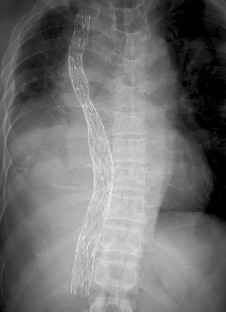

Fig. 2